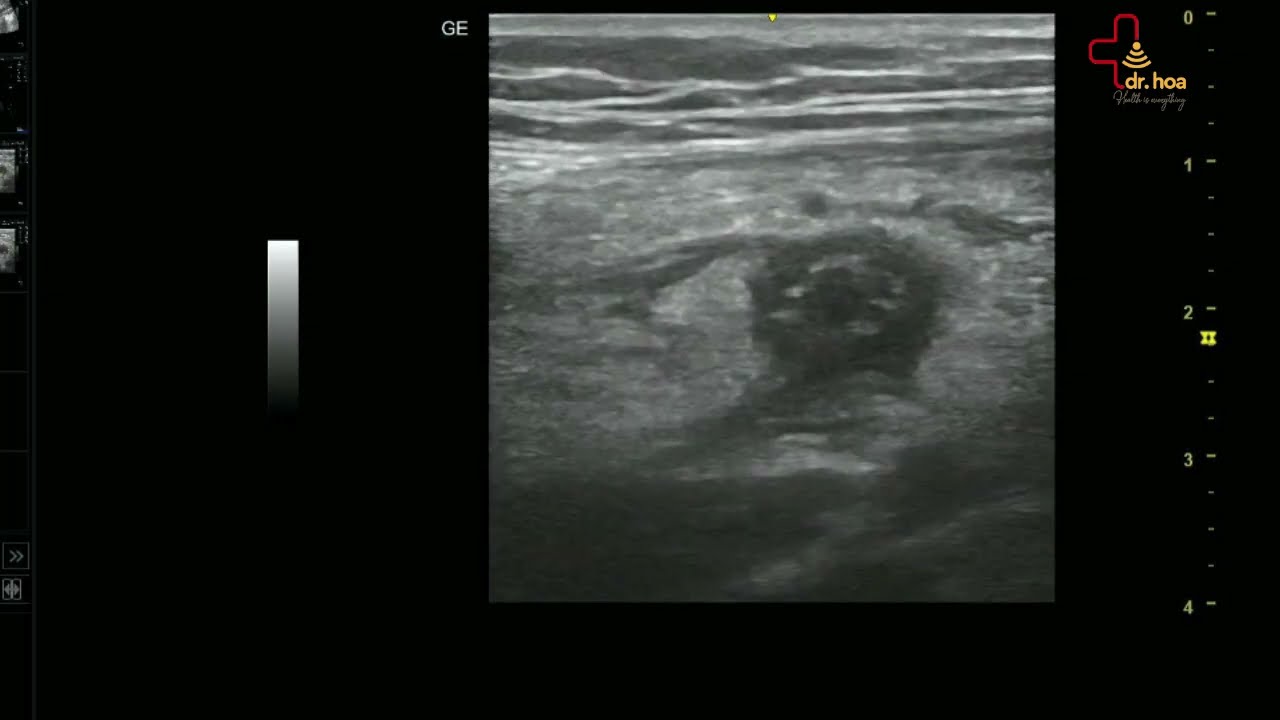

Sieu am Q7 xin gioi thieu case sieu am tuyen vu Buou soi tuyen dien hinh thuong gap o phu nu tre

Siêu âm Q7 xin giới thiệu case #siêu_âm_tuyến_vú : Bướu sợi tuyến điển hình thường gặp ở phụ nữ trẻ!